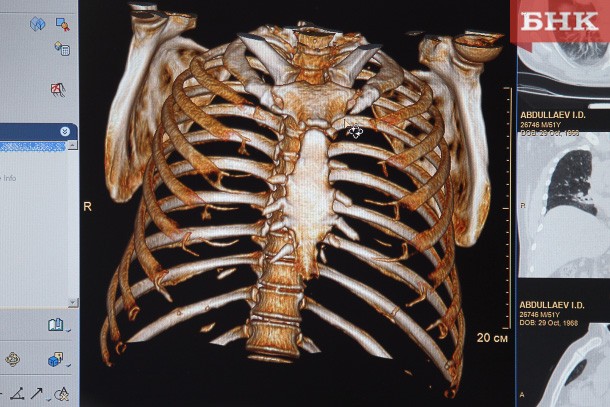

Провоцирует ли пассивное курение болезнь легких

Один из первых признаков хронической болезни легких — одышка. Подвержены ей прежде всего курильщики, которые также ставят в опасное положение свое окружение.

По словам врача-пульмонолога из Республиканской клинической больницы Оксаны Андроновой, распознать хроническую обструктивную болезнь легких (ХОБЛ) можно по наличию прогрессивной одышки. Также у больного чаще бывают простудные заболевания, появляется кашель с отделением слизи. Снижается работоспособность, повышается утомляемость, а при дыхании появляются хрипы, которые слышны на расстоянии.